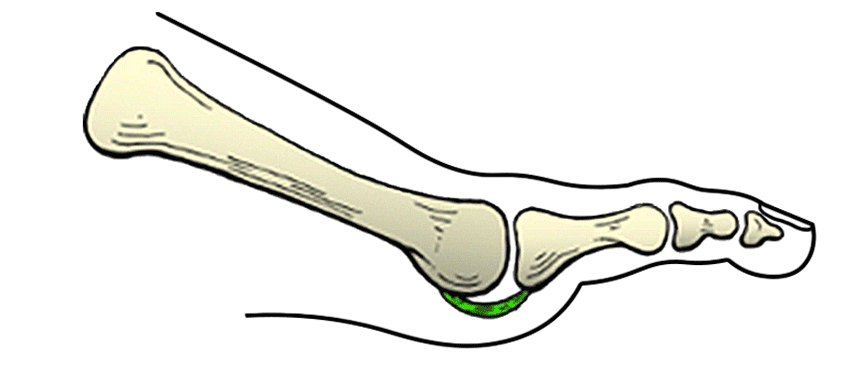

A placa plantar é uma forte estrutura fibrocartilaginosa de forma trapezoidal que serve de base e apoio para as cabeças dos metatarsos do pé. Ela está intimamente relacionada com diversas estruturas anatômicas que constituem a articulação proximal dos dedos do pé, como a cápsula articular, as fibras da fáscia plantar, os ligamentos articulares (colaterais, transverso e interósseos) e a bainha dos tendões flexores dos dedos.

O ligamento transverso e os ligamentos colaterais conectam as bordas laterais da placa plantar ao osso metatarsal e ao capuz extensor, formando um complexo ligamentar forte e eficiente na estabilização dos dedos do pé.

A placa plantar interliga a cabeça metatarsal à base da falange proximal, servindo como um coxim de apoio e banda de tensão, estabilizando as forças longitudinais e axiais dos dedos do pé. Ela atua impedindo o deslocamento dorsal da articulação com também limita o deslocamento lateral (varo e valgo) do dedo.